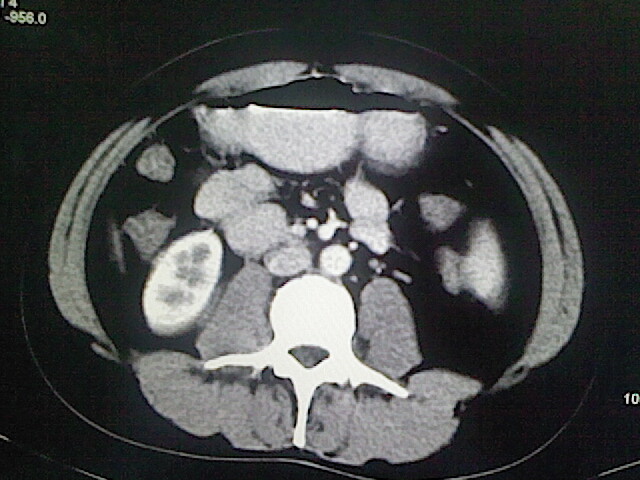

以下是引用卜一在2009-3-14 9:49:00的发言:[br]胆囊萎缩,胆囊壁不规则增厚,内部结构模糊,增强明显强化。另:肝左叶外侧段肝囊肿。支持:慢性胆囊炎!高度可疑:胆囊癌!

以下是引用余辉在2009-3-14 8:48:00的发言:[br]1)慢性胆囊炎。2)肝左叶外侧段肝囊肿。3)脂肪肝。[br]支持,胆囊萎缩,密度增高,不知b超具体有何提示,钙胆汁?结石?

以下是引用jiangjing在2009-3-14 10:18:00的发言:[br]1)慢性胆囊炎。2)肝左叶外侧段肝囊肿。3)脂肪肝。4.】建议行肝功能检查